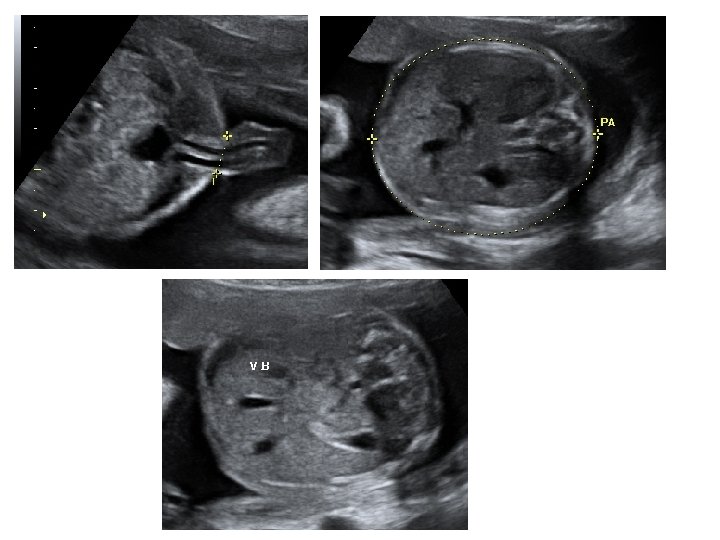

Échographie du 2ème trimestre • Entre 21 et 23 SA • Évaluer la croissance fœtale - pôle céphalique BIP : diamètre bipariétal PC : périmètre céphalique - abdomen fœtal CA : circonférence abdominale - extrémités : LF : longueur fémorale

• Étude morphologique approfondie - pôle céphalique : contours de la boite crânienne, volume des ventricules latéraux, structures de la ligne médiane, cervelet (aspect et mesure de sa largeur) - distance inter-orbitaire - coupe nez-lèvre - profil : menton aligné avec le front, mesure des OPN

- thorax : cœur (position, 4 cavités équilibrées, septum inter ventriculaire, croisement Ao/AP), poumons - abdomen : paroi intègre, estomac (position, volume), vésicule biliaire, intestin grêle - arbre urinaire : vessie (position, volume), 2 reins - sexe - rachis avec son revêtement cutané - membres : 4 x 3 segments, 5 doigts aux 2 mains, mouvements d’ouverture des mains, mesure du pied